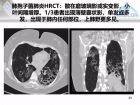

图片标题 肺气肿、囊性肺部疾病的影像学病因鉴别